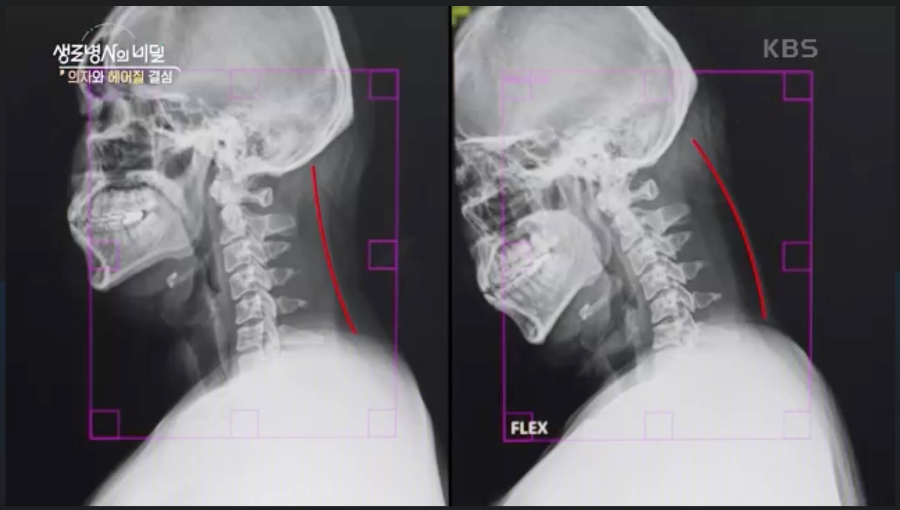

뿐만 아니라 장시간 컴퓨터 모니터를 바라보면서 목의 후만 변형이 일어났다. 목의 퇴행성 변화도 함께 관찰되고 있다.